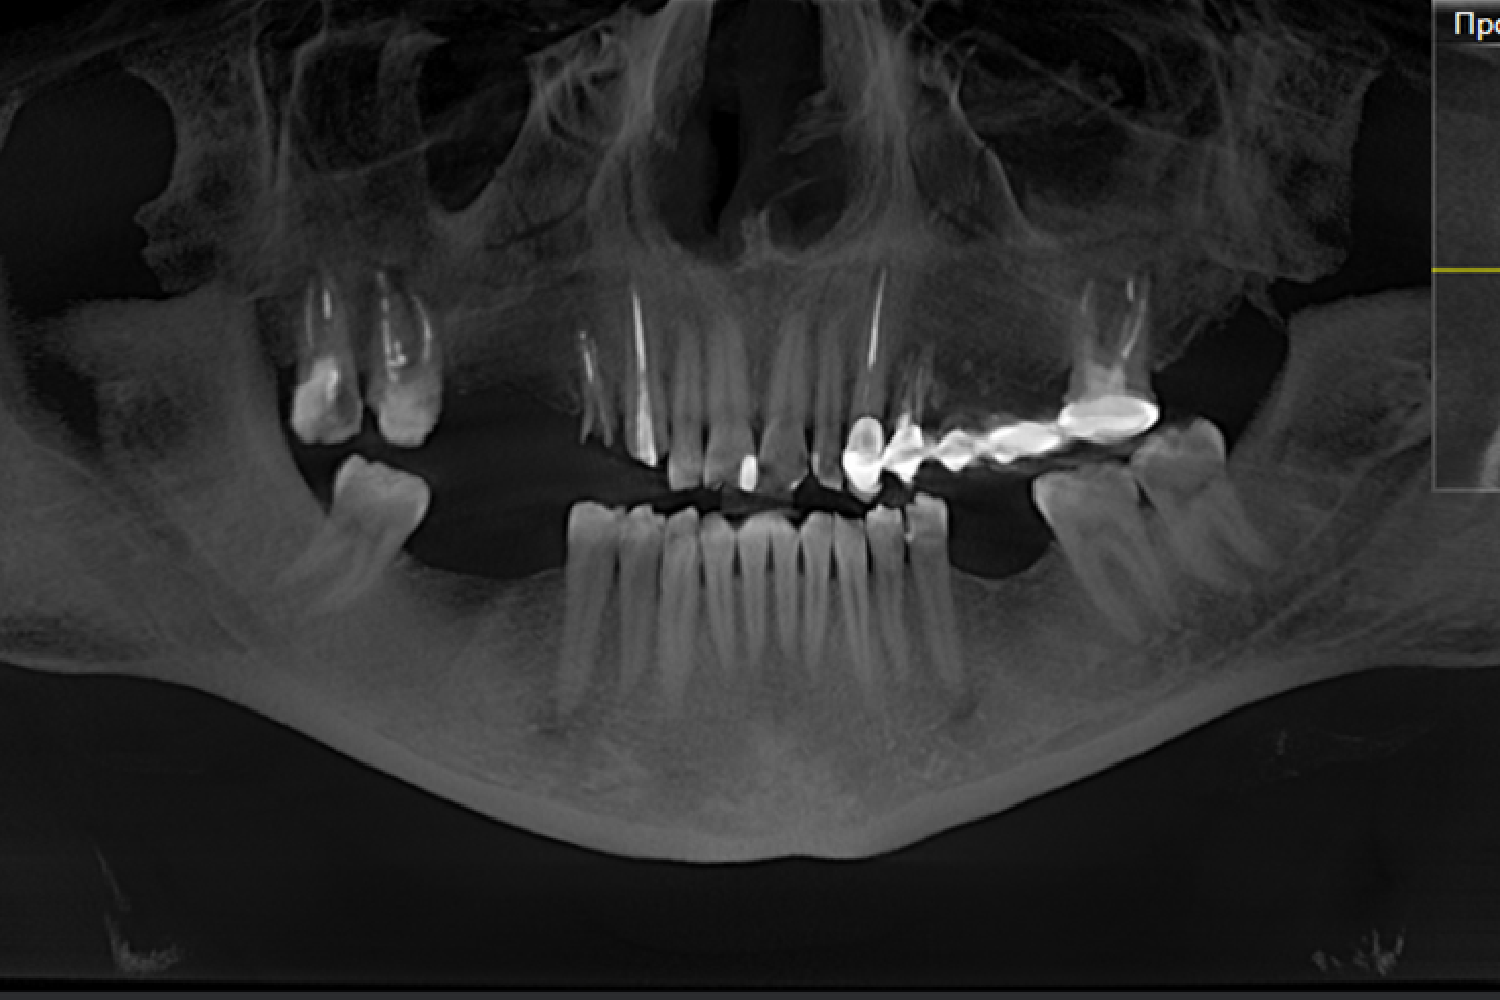

На цей раз, пацієнтка звернулась зі скаргою на розцементування конструкцій. Під час діагностики було виявлено переломи зубного коріння четвертого зуба зліва, пʼятого зуба справа на верхній щелепі, а також патологічне стертя зубів внаслідок порушення прикусу.

Огляд лікаря, повна діагностика ротової порожнини та узгодження плану лікування.